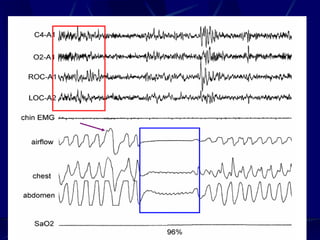

Nocturnal Polysomnography-in lab

study, where EEG, EMG, HR, body

position, leg movements, Oximetry,

Snoring, abdominal and chest wall

movements are recorded